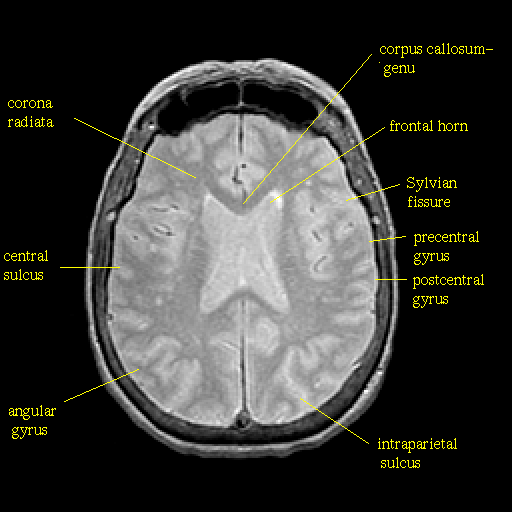

Proton density-weighted structural MR: Slice 32

Slice 32